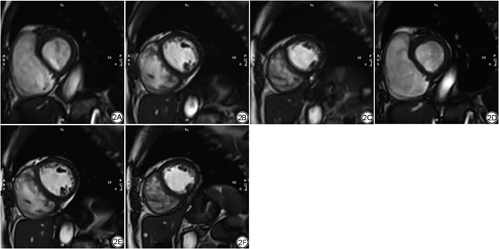

两种电影序列所获取的所有图像由两位放射科医师评估(LYY:3年工作经验,初级职称;LL:10年工作经验,中级职称)。采用主观评价(5分标准[12]:5=极好的图像质量;4=正常的图像质量;3=图像存在伪影但不影响诊断;2=心室周围存在严重的伪影;1=图像存在严重伪影难以诊断)、欧洲CMR质量评估标准[18]及边缘锐利度定量分析[19](Image J:2.3.0,NIMH)对图像质量进行评价(图1),如有分歧讨论后达成一致。CMR图像后处理采用CVI 42软件(Circle Cardiovascular Imaging, 加拿大)。心功能分析通过自动追踪结合手动校正方法勾画舒张末期及收缩末期RV内外膜轮廓,并获取最终结果[20]。RV心肌应变分析通过后处理软件特征追踪模块,在舒张末期勾画4腔长轴及短轴系列电影图像RV内外膜轮廓,自动延伸至整个心动周期后分析得出。图2为两种电影序列采集的图像对比。组内(intra-observer)一致性由一名研究者(LYY)在2周后对随机选择的20例研究对象再次进行RV功能及应变测量后分析得出;组间(inter-observer)一致性由另一位研究者(LL)对上述20例研究对象进行RV功能及应变测量后分析得出。

cine-SegBH的平均扫描时间为(143±42)s,cine-MoCo的扫描时间为(115±24)s,差异具有统计学意义(P<0.05)。图像质量主观评价(5分标准)中,cine-MoCo与cine-SegBH的得分分别为(4.4±0.7)及(4.1±0.8),差异具有统计学意义(P<0.05);欧洲CMR质量评估标准评价中,cine-MoCo与cine-SegBH的得分分别为(0.125±0.404)和(0.425±0.844),差异具有统计学意义(P<0.05)(表2)。选取舒张末期4腔长轴电影图像室间隔中点进行图像边缘锐利度测量,结果显示cine-SegBH与cine-MoCo的值分别为(0.064±0.133)及(0.065±0.139),差异不具有统计学意义(P>0.05)。